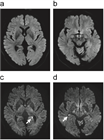

1. 発症1〜3日後の頭部MRI 拡散強調画像で、高頻度に海馬の点状高信号病変を認める。